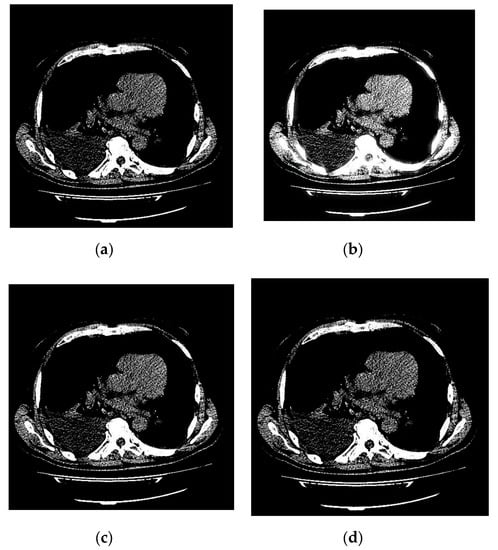

An example of 3D tomographic images “wmri”, “Trufi_COR” and “Body_1.0” DWT with wavelet is shown in Figure 5, Figure 6 and Figure 7 respectively. Frames in Figure 6 and Figure 7 are selected to illustrate the error effect on the image processing result. Figures show a gradual improvement in the quality of processing with an increase the bit-width : in Figure 5b, Figure 6b and Figure 7b visible distortion (Figure 5b is darkened in places, and Figure 6b and Figure 7b are lighted); in Figure 5c, Figure 6c and Figure 7c processed images are indistinguishable by eye from the original images; in Figure 5d, Figure 6d and Figure 7d processed images are identical to the corresponding originals. Experimental results are of higher quality compared with the calculation results. The values dB and at and respectively (Figure 5) obtained after 8-bit image “wmri” DWT with wavelet exceed the corresponding calculated values dB and at and respectively (Table 1). The values dB and at and respectively (Figure 6) obtained after 12-bit image “Trufi_COR” DWT with wavelet exceed the corresponding calculated values dB, dB at and respectively (Table 2). Similarly, for “Body_1.0”.

Figure 5.

Example of 3D tomographic 8-bit image “wmri” DWT by wavelet: (a) original image; processed image: (b) , dB; (c) , dB and (d) , .

The darkening and lighting in Figure 5, Figure 6 and Figure 7 were due to the low accuracy of wavelet filters coefficients quantization used for image processing. The excessive character of quantization error led to an increase in the voxels brightness values of the processed images. Figure 6b and Figure 7b turned out to be lighted since 12- and 16-bit images had a brightness margin, which is shown by the histograms in Figure 4b,c. However, the range of brightness values of the 8-bit image was fully utilized (Figure 4a) and the quantization error led to the computational range overflow. The voxels brightness values that exceeded the range went to zero as a result of this.